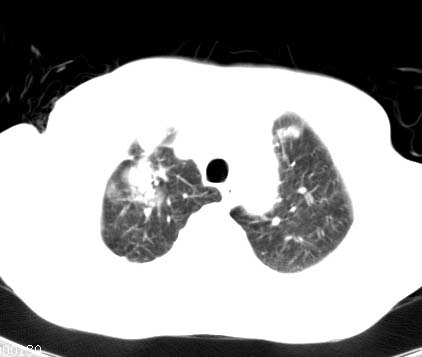

标题: CT14027:男性病人 71岁 咳嗽咳痰数周. [打印本页]

标题: CT14027:男性病人 71岁 咳嗽咳痰数周.

男性病人 71岁 咳嗽咳痰数周.诊断结核应该有保障吧!

右上肺结核,请结合痰检除外活动期;右上叶支气管官腔狭窄建议支气管镜或抗僗后随诊除外堵塞性改变。

高度怀疑肺癌,强烈要求纤支镜检查。

支持双上肺继发性肺结核。